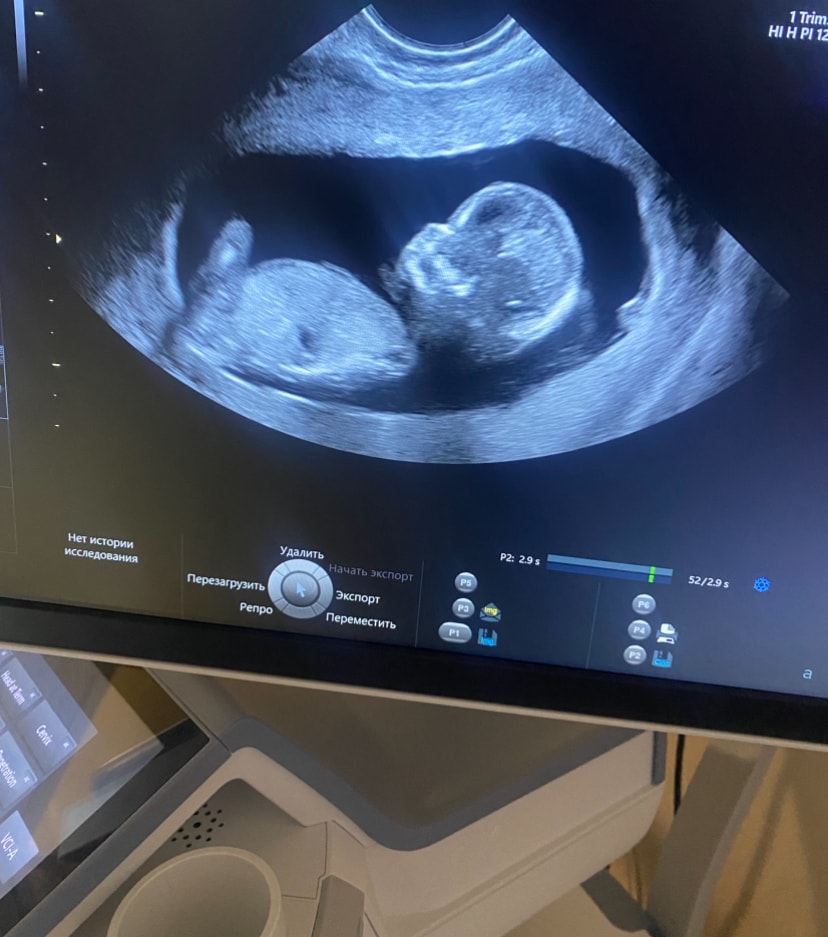

Половой бугорок параллельно спинке - девочка) Ну я такой же эксперт как и вы) Даже Узисты на этом сроке ошибаются. Пока что всё 50/50

Если я правильно вижу, то малыш лежит боком к нам) и пол невозможно разглядеть )

Вроде на девочку похожа, но я тот еще "специалист" 😂

Ставлю на девочку

Я могу только догадаться: девочка ☺️

Похоже на девочку